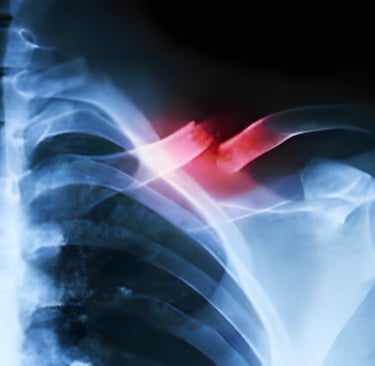

Fractures and Bone Injuries

X-ray imaging is the first-line diagnostic tool for detecting bone fractures and other injuries to the skeletal system. A simple x-ray can determine the location, type, and extent of a fracture, enabling doctors to make decisions on treatment, whether that’s casting, surgery, or other forms of intervention.

Trauma and Emergency Care

For patients with traumatic injuries, x-rays are often used in the ER to quickly identify fractures, dislocations, and other injuries. For instance, in cases of trauma, a chest x-ray may be performed to assess for collapsed lungs, rib fractures, or internal bleeding. The ability to diagnose these conditions rapidly can save lives by ensuring the right treatment is administered immediately.